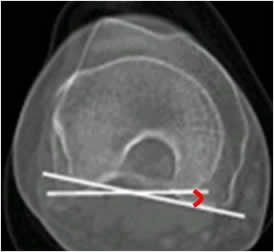

Anteversión femoral:

La medición ideal se realiza con TAC y valora la rotación entre el cuello femoral y los cóndilos femorales. Se mide mediante cortes axiales, que se superponen. Uno sobre el eje del cuello femoral y otro que une la parte posterior de los cóndilos femorales.

(3, 18). (Fig 59, 60 A y B).

Fig 59. Anteversión femoral.

A: TAC axial sobre el cuello femoral, con línea discontinua sobre su eje.

B: TAC axial a nivel de la rodilla. Línea que une la parte posterior de los cóndilos femorales y al superponerla, forma el ángulo de anteversión.